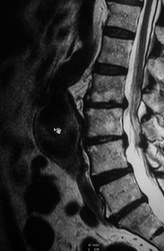

На осмотре заметен отек в виде муфты выше голеностопного сустава, клинические тесты показывают признаки перелома. Рентген подтвердил предварительный диагноз — стресс- перелом большеберцовой кости (стрелка).

Усталостный или стрессовый перелом — результат накопившихся микротравм кости из-за слишком больших физических нагрузок. При этом утомленные мышцы не справляются с ударной нагрузкой и передают ее на кости, вызывая их повреждение.